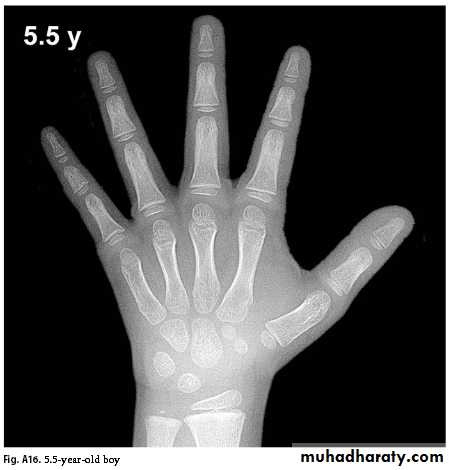

Bone Age

Greulich & Pyle: Radiographic Atlas of Skeletal Development of the Hand and Wrist, This method involves a complex comparison of all the bones in the hand and wrist against reference radiographs of different ages.Delay of 2 years or more in bone age is significant.